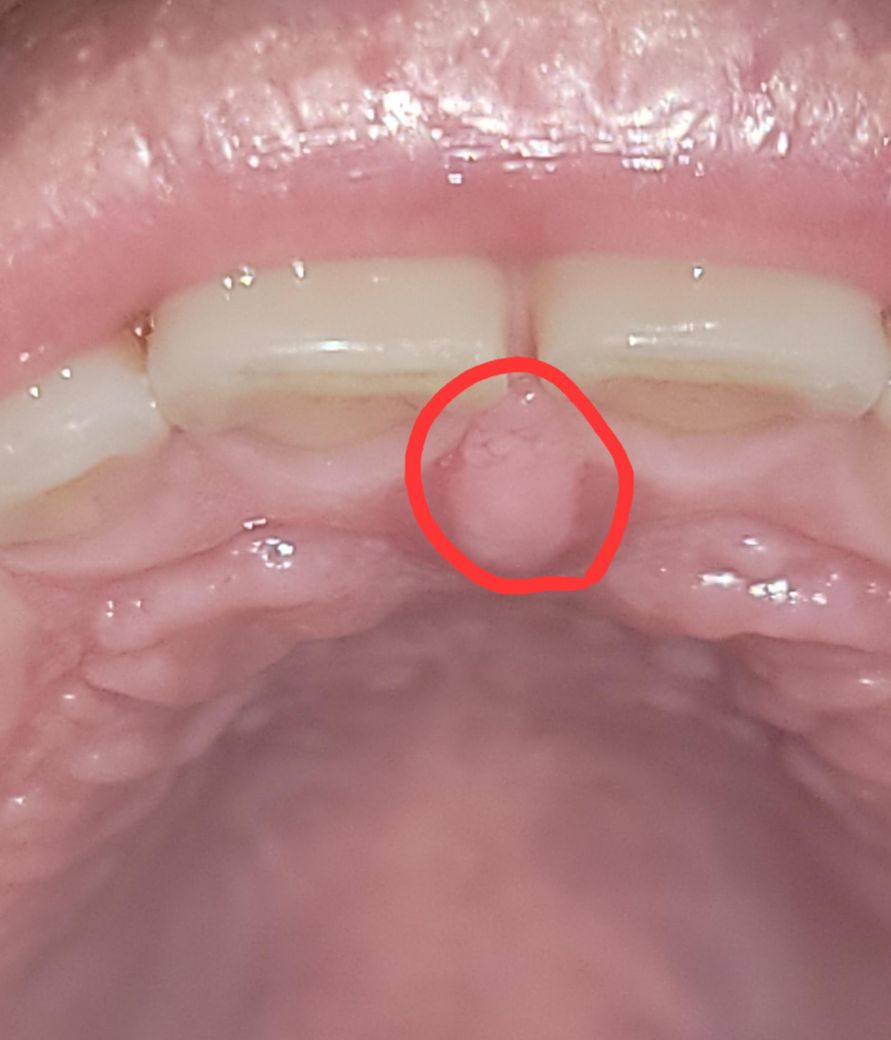

윗니 바로 뒷쪽 잇몸이 따가운게 오래 갑니다.

벌써 5일째 윗니 입천장에 볼록한 부분이 따갑습니다.

그리고 사진에 빨간 동그라미 왼쪽 상단 부분에 표면이 좀 울퉁불퉁한데 이건 정상적인건가요?

표시한 부위는 정상적으로 구개부에 있는 구조물입니다. 해당 부분에는 신경 줄기가 나오는 부분으로 볼록하게 나와 있으며 구개부의 형태는 울퉁불퉁하게 생겼습니다. 해당 부위는 일부러 자극하지 않는 것이 좋습니다

해당 부위는 interdental papilla 라는 부위이고 구강위생관리 부족 등으로 잇몸에 염증이 있거나 뜨겁거나 매운 음식 등에 의해 자극이 되면 부어오를 수 있습니다. 스케일링을 받았으니 좀 기다려보고 증상이 완화되는지 보시기 바랍니다.